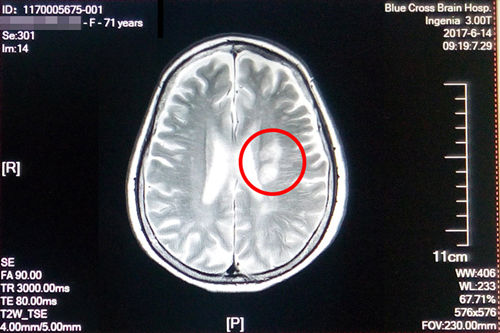

盛阿姨今年五月脑梗复发,在其他医院经过治疗后有所好转,在之后的康复治疗过程中病情又加重了,焦急的家属联系到了“蓝十字”。经过神经内科初步检查诊断,盛阿姨左侧侧脑室旁脑梗塞(急性期),脑干、双侧基底节区及额、顶叶多发腔隙性梗塞;大面积脑梗还造成了言语不清和偏瘫。入院时,右上肢肌力3级,左上肢肌力4级,双下肢肌力3级,因此无法行走,病情较重。

术前磁共振影像显示:患者多发性大面积脑梗